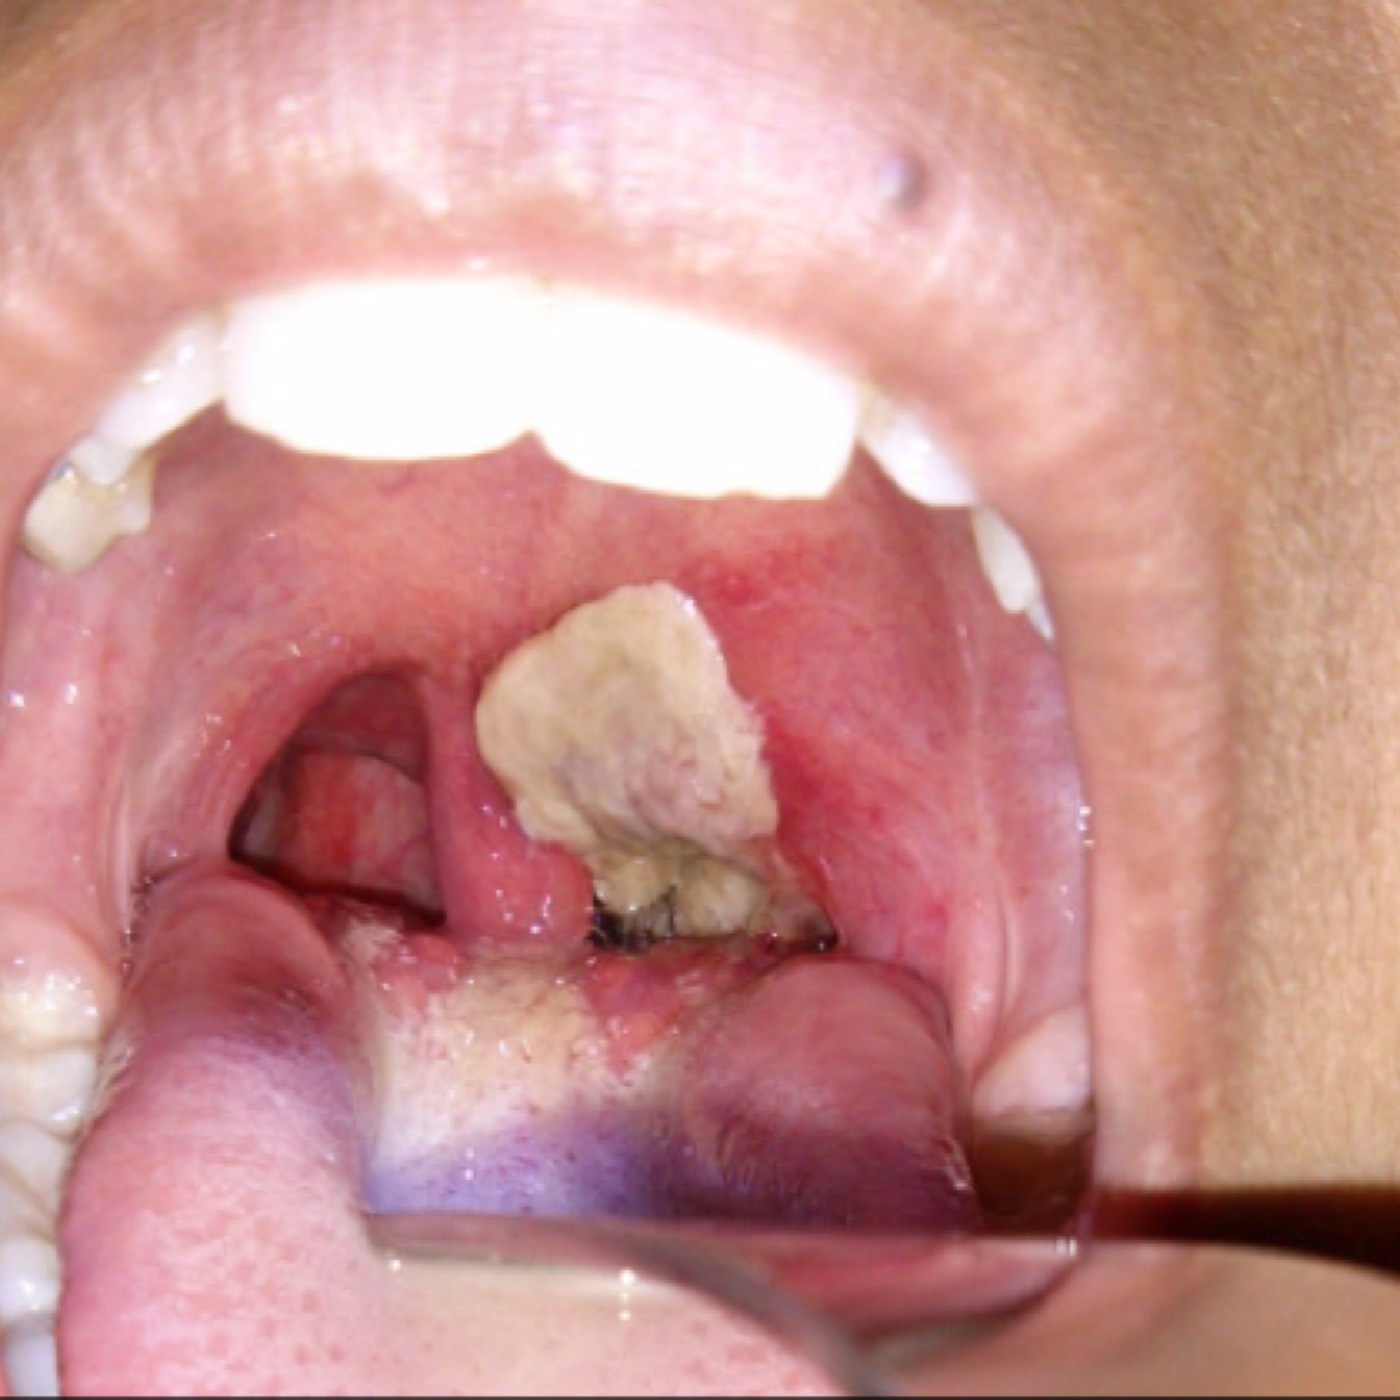

Contributor: Ricky Dhaliwal, MD Educational Pearls: Angioedema in anaphylaxis Histamine and mast cell-mediated pathway Treatment: First line: epinephrine for vasoconstriction and bronchodilation Second line: H1 and H2 antihistamines such as Benadryl and famotidine ACE inhibitor-induced angioedema Different pathway from anaphylaxis ACE inhibitor-induced angioedema is mediated by bradykinins Therefore, anaphylaxis medications are not beneficial in patients with ACE inhibitor-induced angioedema Leading cause of drug-induced angioedema in the US Patients most commonly present with swelling of the lips, tongue, or face Treatment: Airway management: varies depending on the severity and progression of the presentation If awake nasointubation is required, LMX is a 5% lidocaine water-soluble solution that provides anesthesia to the oropharynx Medications: Icatibant is a synthetic bradykinin B2-receptor antagonist that can be used in acute treatment Tranexamic acid (TXA) inhibits the plasmin-dependent formation of bradykinin, but the data on this treatment are mixed and limited Fresh frozen plasma (FFP) is thought to degrade high levels of bradykinin with subsequent resolution of angioedema Discontinue ACE inhibitor References Bork K, Wulff K, Hardt J, Witzke G, Staubach P. Hereditary angioedema caused by missense mutations in the factor XII gene: clinical features, trigger factors, and therapy. J Allergy Clin Immunol. 2009 Jul;124(1):129-34. doi: 10.1016/j.jaci.2009.03.038. Epub 2009 May 27. PMID: 19477491. Bova M, Guilarte M, Sala-Cunill A, Borrelli P, Rizzelli GM, Zanichelli A. Treatment of ACEI-related angioedema with icatibant: a case series. Intern Emerg Med. 2015 Apr;10(3):345-50. doi: 10.1007/s11739-015-1205-9. Epub 2015 Feb 10. PMID: 25666515. Karim MY, Masood A. Fresh-frozen plasma as a treatment for life-threatening ACE-inhibitor angioedema. J Allergy Clin Immunol. 2002 Feb;109(2):370-1. doi: 10.1067/mai.2002.121313. PMID: 11842313. Pathak GN, Truong TM, Chakraborty A, Rao B, Monteleone C. Tranexamic acid for angiotensin-converting enzyme inhibitor-induced angioedema. Clin Exp Emerg Med. 2024 Mar;11(1):94-99. doi: 10.15441/ceem.23.051. Epub 2023 Aug 1. PMID: 37525579; PMCID: PMC11009700. Simons FE. First-aid treatment of anaphylaxis to food: focus on epinephrine. J Allergy Clin Immunol. 2004 May;113(5):837-44. doi: 10.1016/j.jaci.2004.01.769. Erratum in: J Allergy Clin Immunol. 2004 Jun;113(6):1039. Dosage error in article text. PMID: 15131564. Summarized by Meg Joyce, MS2 | Edited by Meg Joyce & Jorge Chalit, OMS4 Donate: https://emergencymedicalminute.org/donate/